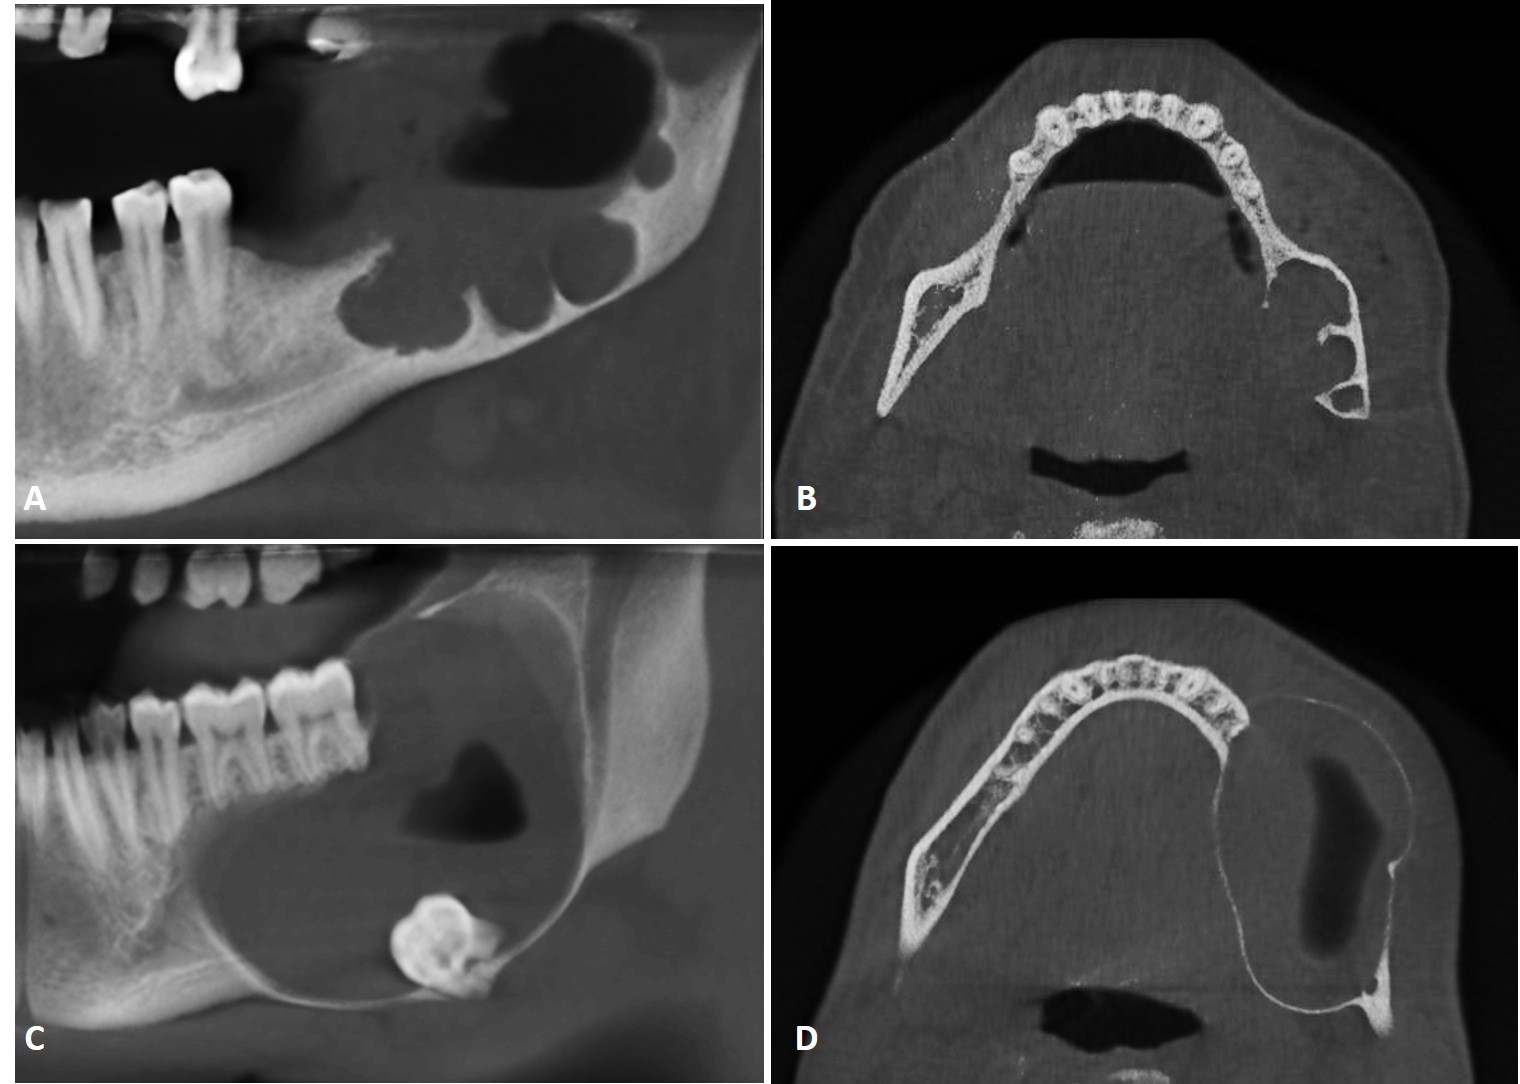

Ameloblastoma is an odontogenic tumor that shares clinical and imaging characteristics with other lesions of the jaws, such as odontogenic keratocyst, which makes the diagnosis difficult. However, in addition to radiographic and tomographic examinations, Magnetic Resonance Imaging (MRI) has been increasingly used, contributing with relevant additional information about the differentiation between solid and liquid components of the lesion. This case report was conducted to present two variations of ameloblastoma and discuss the radiographic, tomographic and MRI contribution in the differential diagnosis between ameloblastoma and odontogenic keratocyst.The signal intensity in T1-weighted MRI revealed internal fluid content in both cases, which was important in the differential diagnosis with other intraosseous lesions such as odontogenic keratocysts. This is probably due to the presence of keratin that increases the viscosity of the content and also for an intermediate signal intensity signal in T2-weighted MRI. Therefore, MRI revealed important internal characteristics of the reported lesions, which was very useful in the establishment of the differential diagnosis with other lesions.